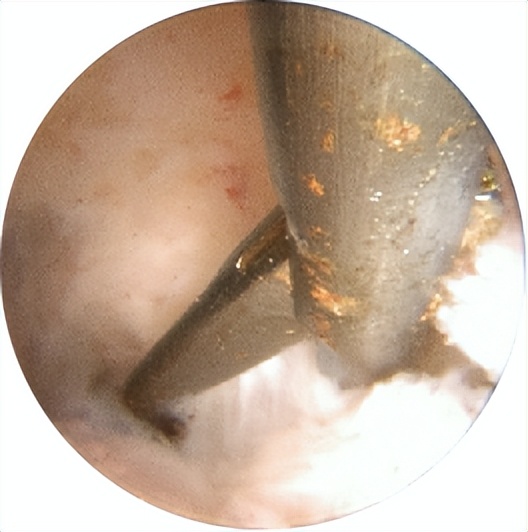

△宫腔镜下见粘连带分隔宫腔形成不规则空间

△宫腔镜下微型剪刀分离宫腔粘连